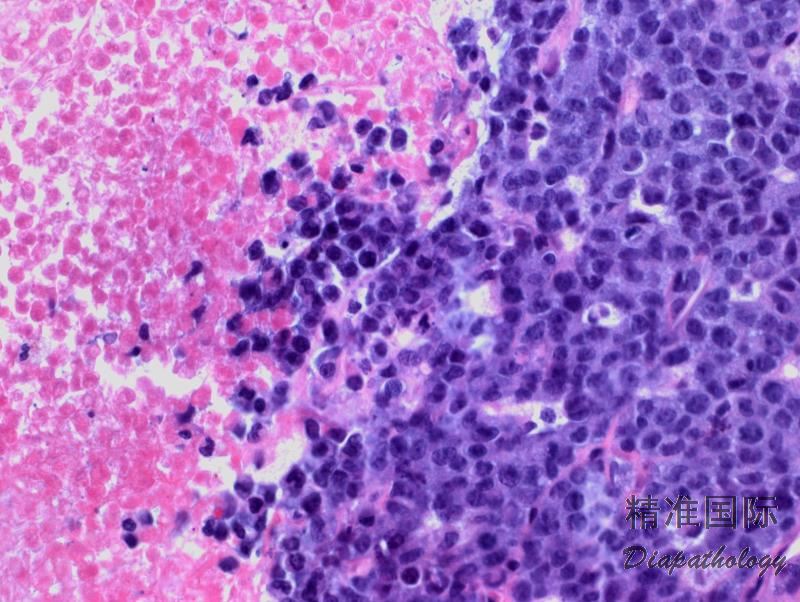

肿瘤细胞弥漫增生,常呈粘附性生长和窦内寝润。

肿瘤细胞形态谱系较宽,从主要是较小细胞到全是异性大细胞。根据肿瘤细胞大小、形态、浸润方式和背景细胞成分等分为多种模式。多数病例(常见模式,占 60%)由多形性大细胞构成,细胞胞质丰富、常透明、嗜碱性或嗜酸性,核染色质通常细块状或散在分布,可有多个核仁。此外,还有小细胞模式(5-10%),淋巴组织细胞模式(10%),霍奇金样模式(3%),或混合/复合模式(15%)。偶有病例肿瘤细胞稀少,伴背景粘液样改变,或有很多梭形细胞,呈现肉瘤样改变。无论什么生张模式,都含有数量不等的 CD30+“标志性细胞”,其形态特征为异型大细胞含偏位马蹄样或肾形核,核周常有嗜酸性区域。

- 普通型 ALCL :最多见(60%)。肿瘤由多形大细胞包括标志性细胞构成,但也可是较单一的卵圆形核细胞混合多形型大细胞,通常呈粘附性生长,可见特征性窦内浸润。